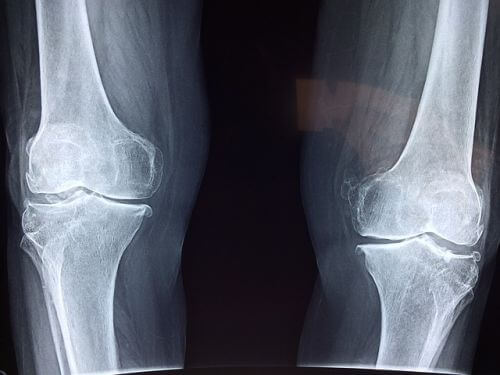

베이커 낭종은 퇴행성 무릎관절염, 반월상연골 파열과 같은 무릎의 질환과 큰 관련이 있습니다. 또한 류마티스성 관절염과 같은 염증성 질환이 있으면 인대의 이완도가 변하여 베이커 낭종이 생길 수도 있습니다.베이커 낭종의 임상 증상

베이커 낭종을 확인하기 위해선 임상적인 평가가 주로 사용됩니다. 대부분의 낭종은 반막양근과 종아리근육의 안쪽 머리 사이에 위치해 있으며, 낭종이 커진 경우에는 육안으로 보거나 만질 수 있습니다, 대부분의 경우 X선(XR)은 정상으로 나타납니다. MRI는 특별히 필요하지 않으며,